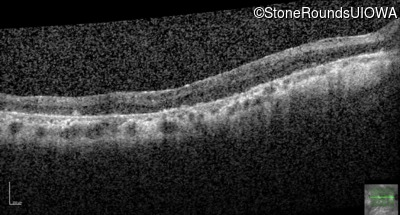

Visit at age: 35 years

Optical Coherence Tomography - Right - 20/100 +1

Exemplar / OCT Stack